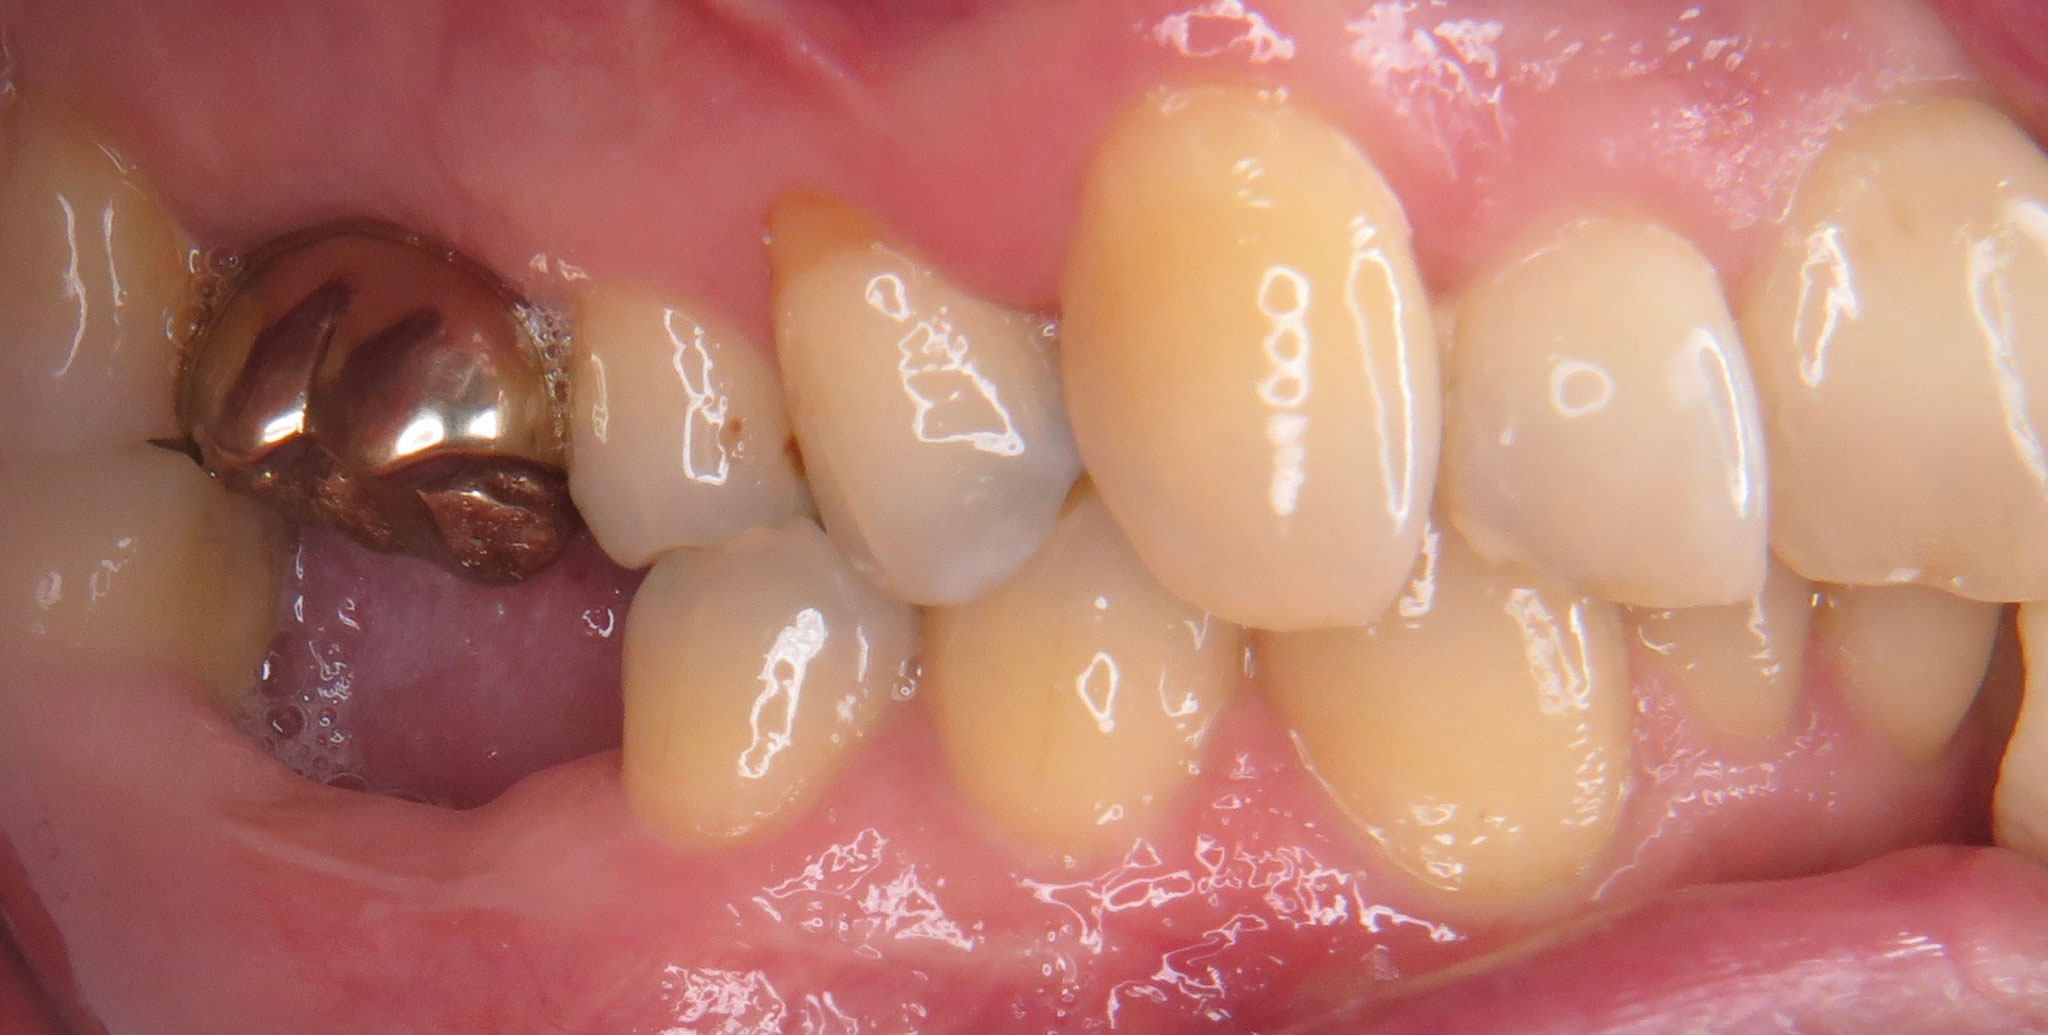

Muss Ein Fehlender Backenzahn Ersetzt Werden. Fehlender Seitenzahn im Unterkiefer ersetzt durch ein Keramikimplantat der Implantatexperte Aber natürlich müssen auch fehlende Backenzähne so schnell wie möglich ersetzt werden - auch wenn die Lücke dort nicht unmittelbar sichtbar ist. Welche Zähne müssen nicht ersetzt werden? Ein fehlender Zahn in Ihrem Alter und an dieser Stelle (zweiter grosser Backenzahn oder Zahn Nr

Der Kieferknochen wird abgebaut und die Muskulatur verändert sich. Welche Zähne müssen nicht ersetzt werden? Ein fehlender Zahn in Ihrem Alter und an dieser Stelle (zweiter grosser Backenzahn oder Zahn Nr

Zum einen fällt ein fehlender Frontzahn sofort ins Auge Ein Bekannter hat seit Jahren eine ähnliche Lücke und keinerlei Probleme Aber natürlich müssen auch fehlende Backenzähne so schnell wie möglich ersetzt werden - auch wenn die Lücke dort nicht unmittelbar sichtbar ist.

Vorher Nachher Bilder Parodontologie 🦷 Dr. med. dent. Ulf Schladebach. Welche Zähne müssen ersetzt werden? Ein fehlender Zahn im hinteren Bereich muss ab einem bestimmten Alter nicht zwingend ersetzt werden Zum anderen nehmen die Frontzähne beim Kauen (Abbeißen) und Sprechen (Lautbildung) besonders wichtige Funktionen ein